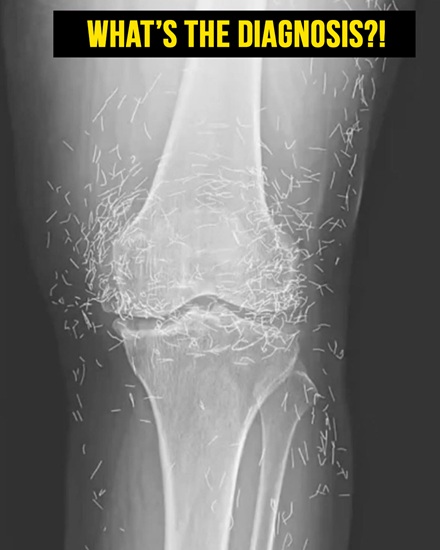

In this woman’s case, imaging studies revealed multiple gold needles embedded deep within her knee joints. Radiologists were surprised by the density and number of retained objects, which created both clinical interest and concern.

In her case, the needles—believed to be gold—were left inside her knees intentionally. This practice, known as intradermal or retained acupuncture, is intended to provide continuous stimulation to the joint and prolong therapeutic effects.

In South Korea, inserting tiny sterile gold threads around a joint is a traditional treatment for osteoarthritis. This method is thought to stimulate blood flow, promote healing, and reduce pain, although rigorous scientific validation is still lacking.

Modern imaging techniques, including X-rays and MRIs, can detect these embedded needles. Radiologists must consider retained metal when interpreting images, as it can interfere with diagnostic clarity and obscure underlying conditions.

The case has drawn attention in medical literature, including the New England Journal of Medicine, as an unusual example of retained gold needles and the potential complications associated with alternative therapies for osteoarthritis.